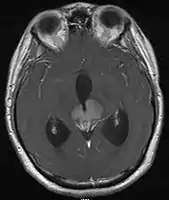

- Mainly located in midline structures, suprasellar region or pineal gland, also basal ganglia and hypothalamus

- Pineal Gland Germinoma

- Suprasellar Germinoma